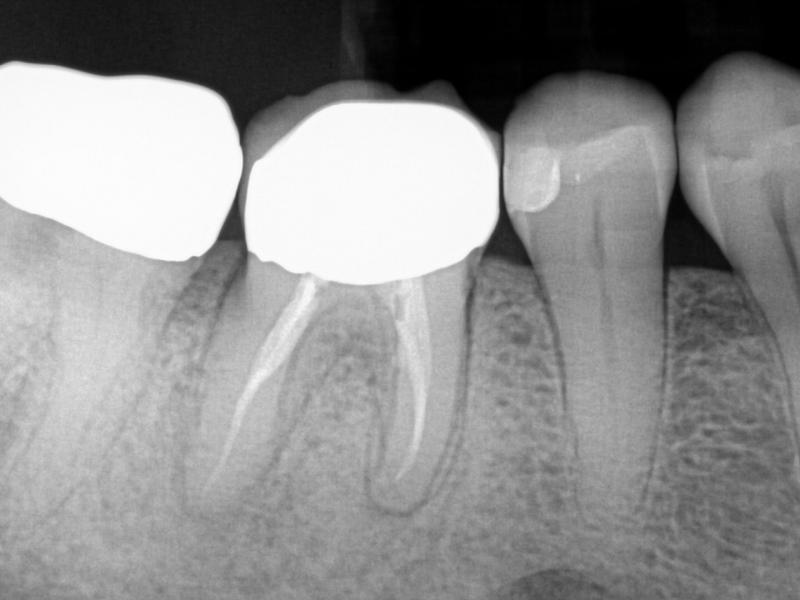

C-Shaped Canal

Karen S. Potter, DDS

View Case Images